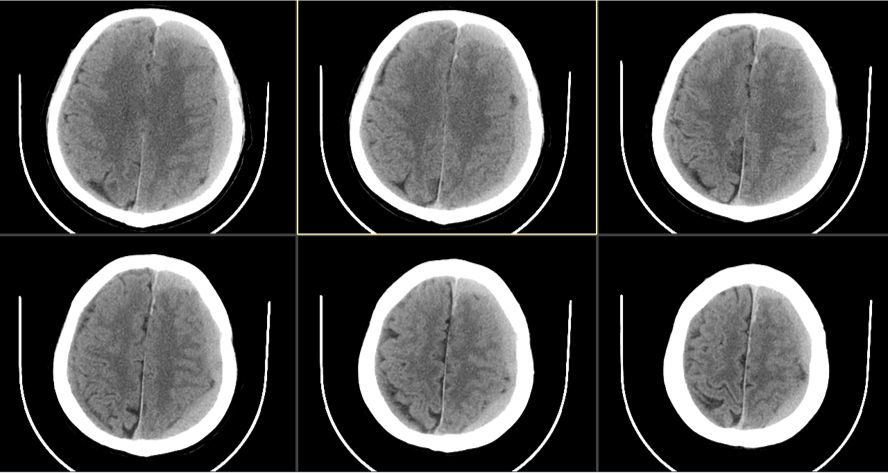

患者约2个月前无明显诱因(否认外伤史)间断出现头痛,头痛为胀痛,左侧较明显,恶心未吐,食欲、睡眠尚可,未予特殊诊治,1个月前患者头痛逐渐加重,思睡,反应略迟钝,行头部CT检查示“慢性硬膜下血肿(双侧)”,于2018年12月15日行颅骨钻孔引流术(左)。术后9天患者恢复良好出院。出院后2周于2019年1月9日患者头痛再次加重,伴有反应迟钝,走路困难,疲乏无力再次就诊,头部CT示“慢性硬膜下血肿(右侧)”,当日再次行颅骨钻孔引流术(右)。术后患者一般状态逐渐好转,无抽搐,无尿便失禁。

2018年12月14日第一次入院

自诉偶有头痛,生活自理。查:神志清,反应迟钝,少语,血压160/95mmHg,颈软,右侧肌力IV级。

2018年12月16日术后第一日

自诉头痛明显缓解。查:神清语明,血压145/85mmHg,颈软,四肢肌力V级。

2018年12月24日出院当日

术后当日(2019年1月16日)

术后3天(2019年1月18日)